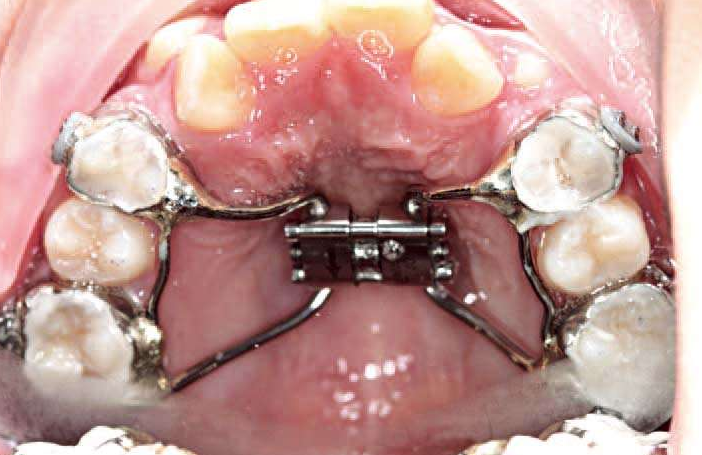

解决方案:粘结式RME配合前方牵引。

图14 RME

图15 粘结式RME

年轻恒牙列,如果上4已经完全萌出,适合做上颌RPE配合前方牵引。

图18 上颌RPE hyrax扩弓

同理,如果上颌牙弓狭窄,咬𬌗会使下颌靠后,如果扩大上颌牙弓,咬𬌗能引导下颌向前。临床上,对于很多的替牙期,下颌后缩的病例,可采用上颌扩弓引导下颌向前的矫治方法。

上颌扩弓,通过“鞋拔子”(foot in shoe)效应,引导下颌向前。

图25 “鞋拔子”效应示意图

图26 上颌四眼簧扩弓